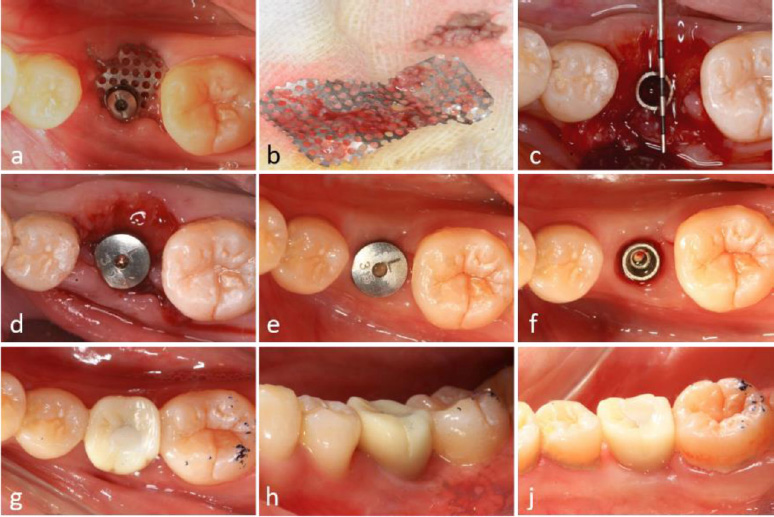

A modified healing abutment was developed to secure a prefabricated titanium mesh on top of the dental implant, ensuring a stable and isolated space beneath the membrane to facilitate osteogenesis in both vertical and horizontal bone defects (Fig. 2a-c).

Local anesthesia (Scandonest 2%, Septodent, Saint-Maur-des-Fosses Cedex, France) was administered for hemostasis. The implant surgical guide template and a novel computer-assisted drill guide template were applied to confirm the implant site (Fig. 3a).

A mid-crestal full-thickness incision was created and extended to teeth 45 and 47 through an intrasulcular incision. Two vertical incisions were performed to prepare a trapezoidal mucoperiosteal flap. The flap was elevated on both the buccal and lingual sides to expose the alveolar crest of the molar space. The depth of the implant socket was 13 mm and confirmed by a guiding drill (the occlusal surface was flush with the crest of the adjacent buccal alveolar ridge) (Fig. 3b).

The implant socket was prepared using osteotomes. A periodontal probe was used to check the integrity of the bone wall, and granulation tissue in the implant socket was completely removed.

Bleeding points (decortication) were created using a round bur to expose the underlying marrow of the alveolar crest. The implant socket was filled with bone material (Bio-Oss, Geistlich, Switzerland). Subsequently, the implant (BASIC 4.5×13 mm) was implanted with a torque of 25 N·cm. A periodontal probe was used to examine the exposure of the implant, with 4 mm on the buccal side and 2 mm on the lingual side (Fig. 3c-i).

The titanium mesh was customized according to the dimensions of the osteogenesis area, measuring 12 mm in height and 22 mm in width. The mesh was trimmed to accommodate the buccal height (10 mm), occlusal surface (8 mm), and lingual side (4 mm). It was then contoured into an “n” shape and trial-fitted to ensure proper adaptation (Fig. 3j). A hole was drilled into the occlusal surface for placement of a modified healing abutment.

2.9. Placement of Titanium Mesh

Bone graft material was applied around the implant neck and the buccal alveolar bone defect. A bioresorbable membrane was then positioned to cover the osteogenesis area and perforated at the implant's using a probe. The titanium mesh was subsequently placed and secured onto the implant using a 0.5 mm modified healing abutment (Fig. 3g-i).

Tension-free closure of the soft tissue using resorbable suturing material (Vicryl 3-0) could not be achieved due to insufficient soft tissue availability. As a result, the titanium mesh remained partially exposed, and a periodontal dressing was applied to protect the surgical site (Fig. 3k).

Approximately two months postoperatively, soft tissue proliferation and epithelization were observed beneath the exposed titanium mesh. Despite the presence of debris and muck adhering to the mesh, no clinical signs of inflammation were detected (Fig. 4a).

During the re-entry procedure, the titanium mesh was found to be encased in dense connective tissue. The mesh was removed six months after the initial surgery, revealing that the space beneath it was occupied by tissue exhibiting macroscopic characteristics of newly formed bone (Fig. 4b, 4c).

Surgical procedure for dental implant placement. (a) Positioning of the surgical guide template, (b) Reflection of a trapezoidal mucoperiosteal flap, (c) Osteotomy and implant placement, (d) Peri-implant bone defect at the cervical region, (e) Buccal vertical bone defect measuring 4 mm; (f) Lingual vertical bone defect measuring 2 mm, (g) Augmentation using alloplastic bone graft material, (h) Application of bioresorbable membrane to cover the graft site, (i) Fixation of titanium mesh using a 0.5 mm modified healing abutment, (j) Contouring of titanium mesh prior to placement, (k) Postoperative exposure of titanium mesh.

Surgical procedures and clinical outcomes of second-stage implant surgery. (a) Intraoral view at 6-month postoperative follow-up, (b) Removal of titanium mesh demonstrating residual debris accumulation, (c) Significant alveolar ridge augmentation and soft tissue formation beneath the titanium mesh, (d) Placement of healing abutment for soft tissue conditioning, (e) Peri-implant soft tissue maturation at 4 months post-healing abutment placement, (f) Establishment of well-contoured peri-implant gingival architecture, (g-i) Intraoral clinical photographs illustrating final prosthetic rehabilitation outcomes.

2.11. Alveolar Ridge Augmentation